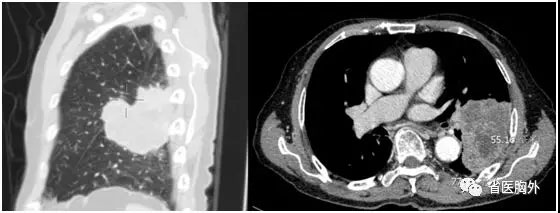

面对如此高龄的患者,在进行了一系列详细检查后,胸外科联合麻醉科、重症医学科、心内科、呼吸科、康复科、内分泌科等相关科室组成多学科团队,对老人的病情进行了全面的分析和讨论:老人的肺部肿物主要位于左下肺叶,并侵犯左上肺多个段,大小约7.7*5.5cm。伴有同侧肺门淋巴结肿大、代谢增高。但全身其他部位未见恶性肿瘤表现。根据术前的影像、检验和临床表现,老人肺部的肿块可以诊断为局部晚期肺癌。对于肺癌而言,目前的综合治疗方法包括手术、化疗、放疗、靶向和生物免疫治疗等,但具体到H老先生身上,年龄和肾功能问题使得化疗不可取,放疗难以覆盖巨大的肿瘤和肺门、纵隔淋巴结等整个区域,风险过高且效果不佳,靶向和免疫治疗需要活检取得组织标本进行基因分析,而患者术前支气管镜未能取得标本,且PET/CT显示肿瘤大部分坏死,穿刺成功率低、风险较大,而病人也拒绝穿刺活检。此外,对于有吸烟史的老年男性患者,靶向治疗的有效率也并不如意,免疫治疗的未知因素更多。在分析讨论了种种治疗方案后,MDT团队最终确认直接手术切除肿瘤是目前的最佳治疗方案。

巨大肿瘤侵犯左肺各叶,必须进行左全肺切除